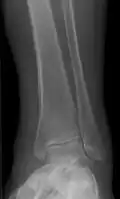

| Periosteal reaction on a healing supracondylar fracture | |